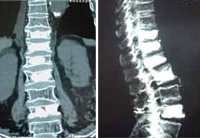

Cifoplastia_08Cifoplastia con balón en cinco niveles realizada por el Dr. Morgenstern. La paciente es una mujer de 80 años, deambulación erecta inmediata